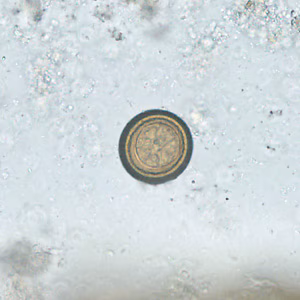

A 42-year-old man with a history of living abroad in Peru for a year returned home to the United States. He reported to his health care provider that he had been experiencing vague intermittent abdominal discomfort. A stool specimen was collected and processed for ova-and-parasite (O&P) examination. Figures A–E show what was observed at 400x magnification in moderate numbers; Figures A and B are of the same object in different focal planes. The object in Figure D is approximately 33 micrometers in diameter. What is your diagnosis? Based on what criteria?

Figure D